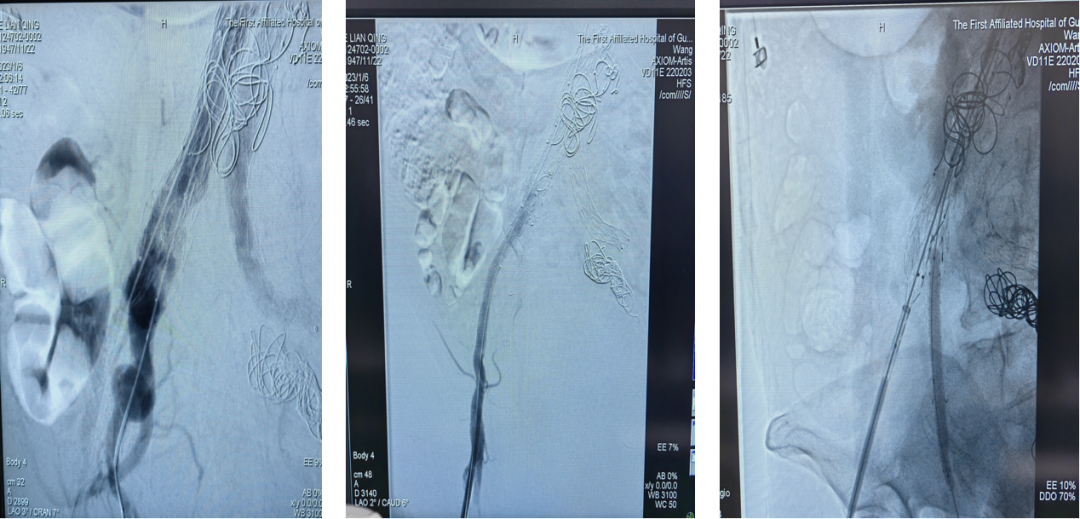

75岁女性 ,AAA合并双侧髂总动脉瘤 ,首次EVAR术后出现内漏 ,采用G-iliac™IBD成功重建右侧IIA ,术后造影效果良好。

左图:EVAR术后;右图:选用IB-1610-080-150,在髂内开口20mm处打开

肱动脉超选髂内,植入PS-C-10080XL,充分后扩

术后造影,效果良好,成功保留髂内动脉